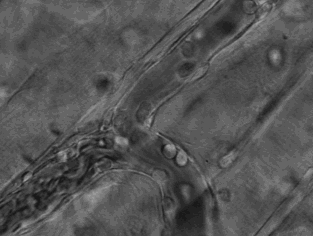

3.這張動圖顯示的是嗜酸性粒細(xì)胞在趨化作用的“感知”下逐漸聚集到一只秀麗隱桿線蟲周圍并對它進(jìn)行攻擊的過程。有“成千上萬”的嗜酸粒細(xì)胞圍聚在線蟲周圍,就像一群螞蟻,善打“包圍戰(zhàn)”。